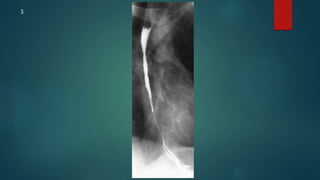

This document appears to be a medical report discussing several patients. It mentions a 35-year-old who was in a severe motor vehicle accident and an 81-year-old with a history of a non-vegetarian diet who had a perforated bowel from a chicken bone. The document provides few other details across its 25 numbered entries and was authored by Dr. Anish Choudhary for junior year 3 on May 30, 2016.